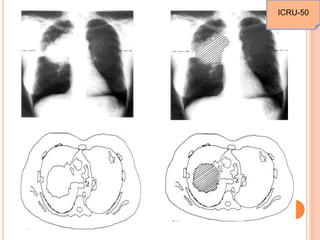

ICRU-50